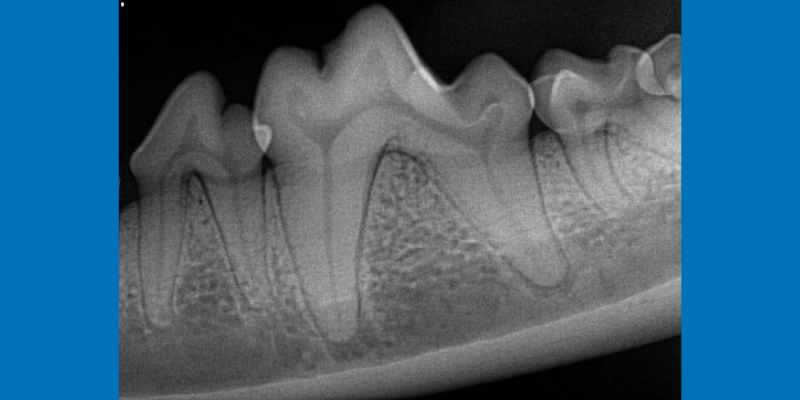

Teeth that look normal to the naked eye can be surprisingly infected below the gumline. In this case, the tooth was so badly infected that the jaw bone was fractured – essential information that a veterinarian needs prior to treatment.

Mandibular molar in a dog. Severe infection has led to jaw fracture (red arrow).